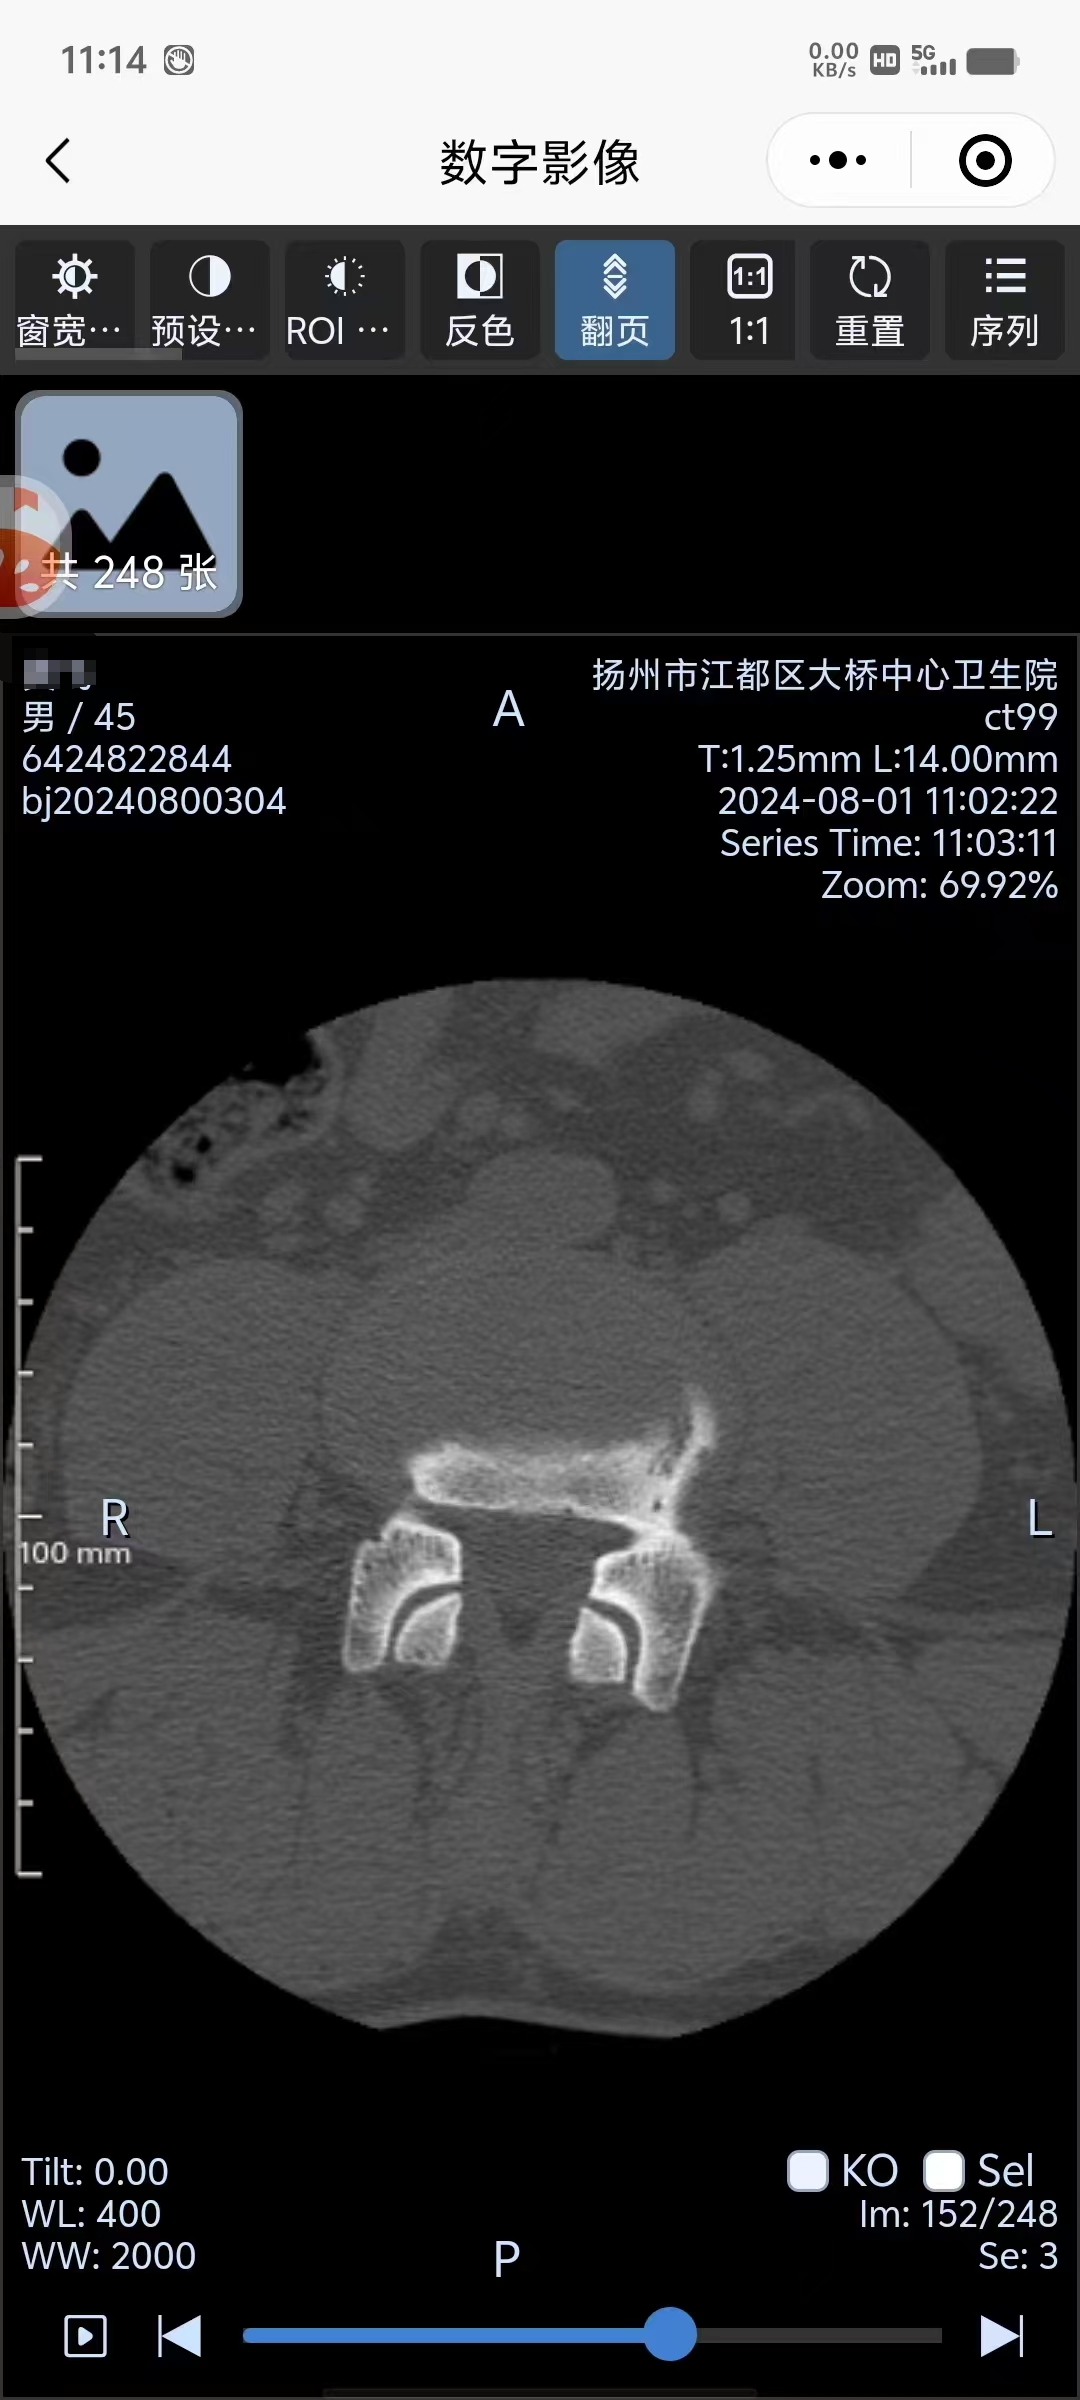

如需电子影像(免费获取“数字云影像”),可下载关注“江都智慧医疗”微信公众号,点击“数字影像”查询电子影像。

操作步骤如下: